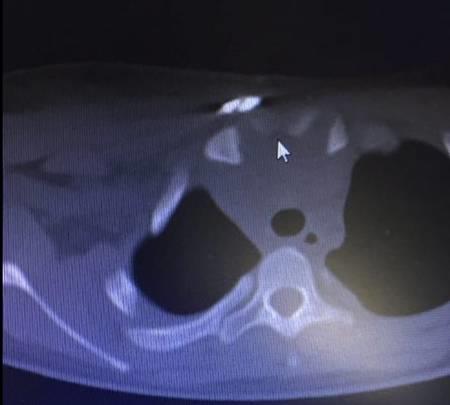

▲CT断层显示上纵膈压迫明显

▲CT断层显示手术复位后上纵膈压迫解除